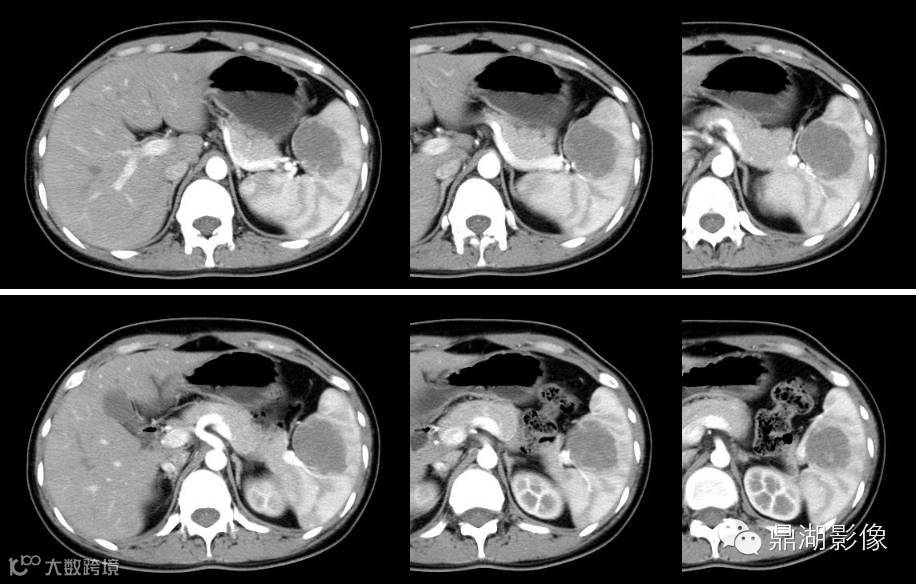

动脉期

门脉期

冠状位

增强扫描特点:动脉期肿块边缘点状及线条样强化,门脉期及延迟期强化渐向中部充填,与脾脏几成等密度,肿块显示渐缩小。是不是让你觉得很简单,但是答案是: